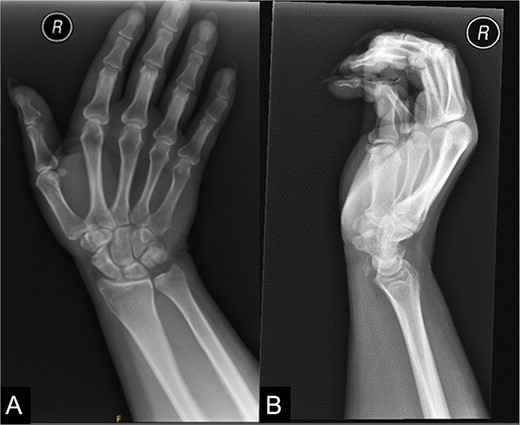

On examination of the right wrist, the patient had a palpable, tender lump in the region of the flexor carpi radialis tendon at the level of the distal radius. There was no associated erythema. Given the pain, the patient had a reduced range of movement during volar flexion of the wrist. There were no abnormalities during a neurovascular examination. Blood investigations were all unremarkable. An X-ray of the right wrist confirmed calcification at the flexor carpi radialis level at the wrist (Fig. 1).

An X-ray of the right wrist which shows calcification at the level of flexor carpi radialis at the wrist.